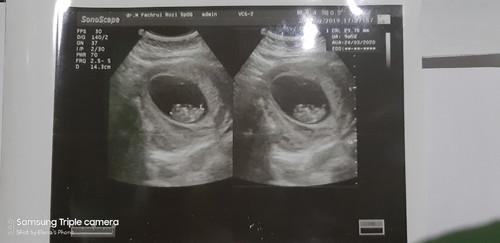

Malam bunda... Puji Tuhan akhirnya saya beranikan USG setelah usg pertama belum terlihat apa2... ternyata UK saya 9w5d kalo menurut HPHT 11week.. Puji Tuhan Semua Baik kata dokternya.. Ukuran bayi sesuai usia, Ketuban cukup dan detak jantung jg baik...